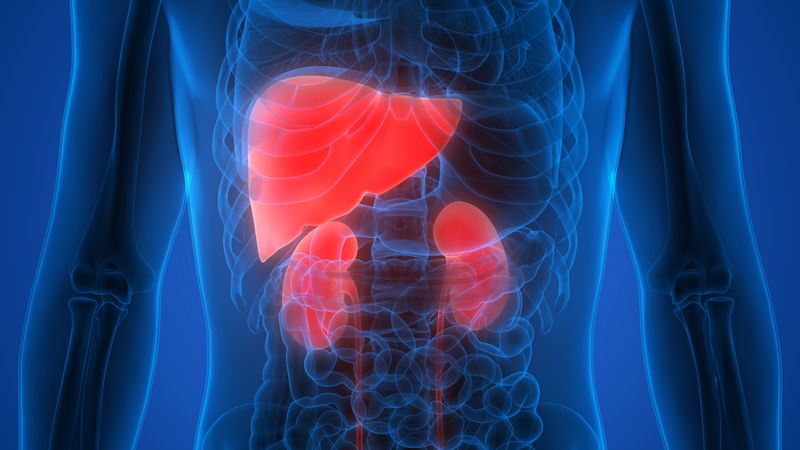

How the opportunistic bacteria P. aeruginosa genetically diversifies during cystic fibrosis infections. Jorth et al./Cell Host & Microbe 2015